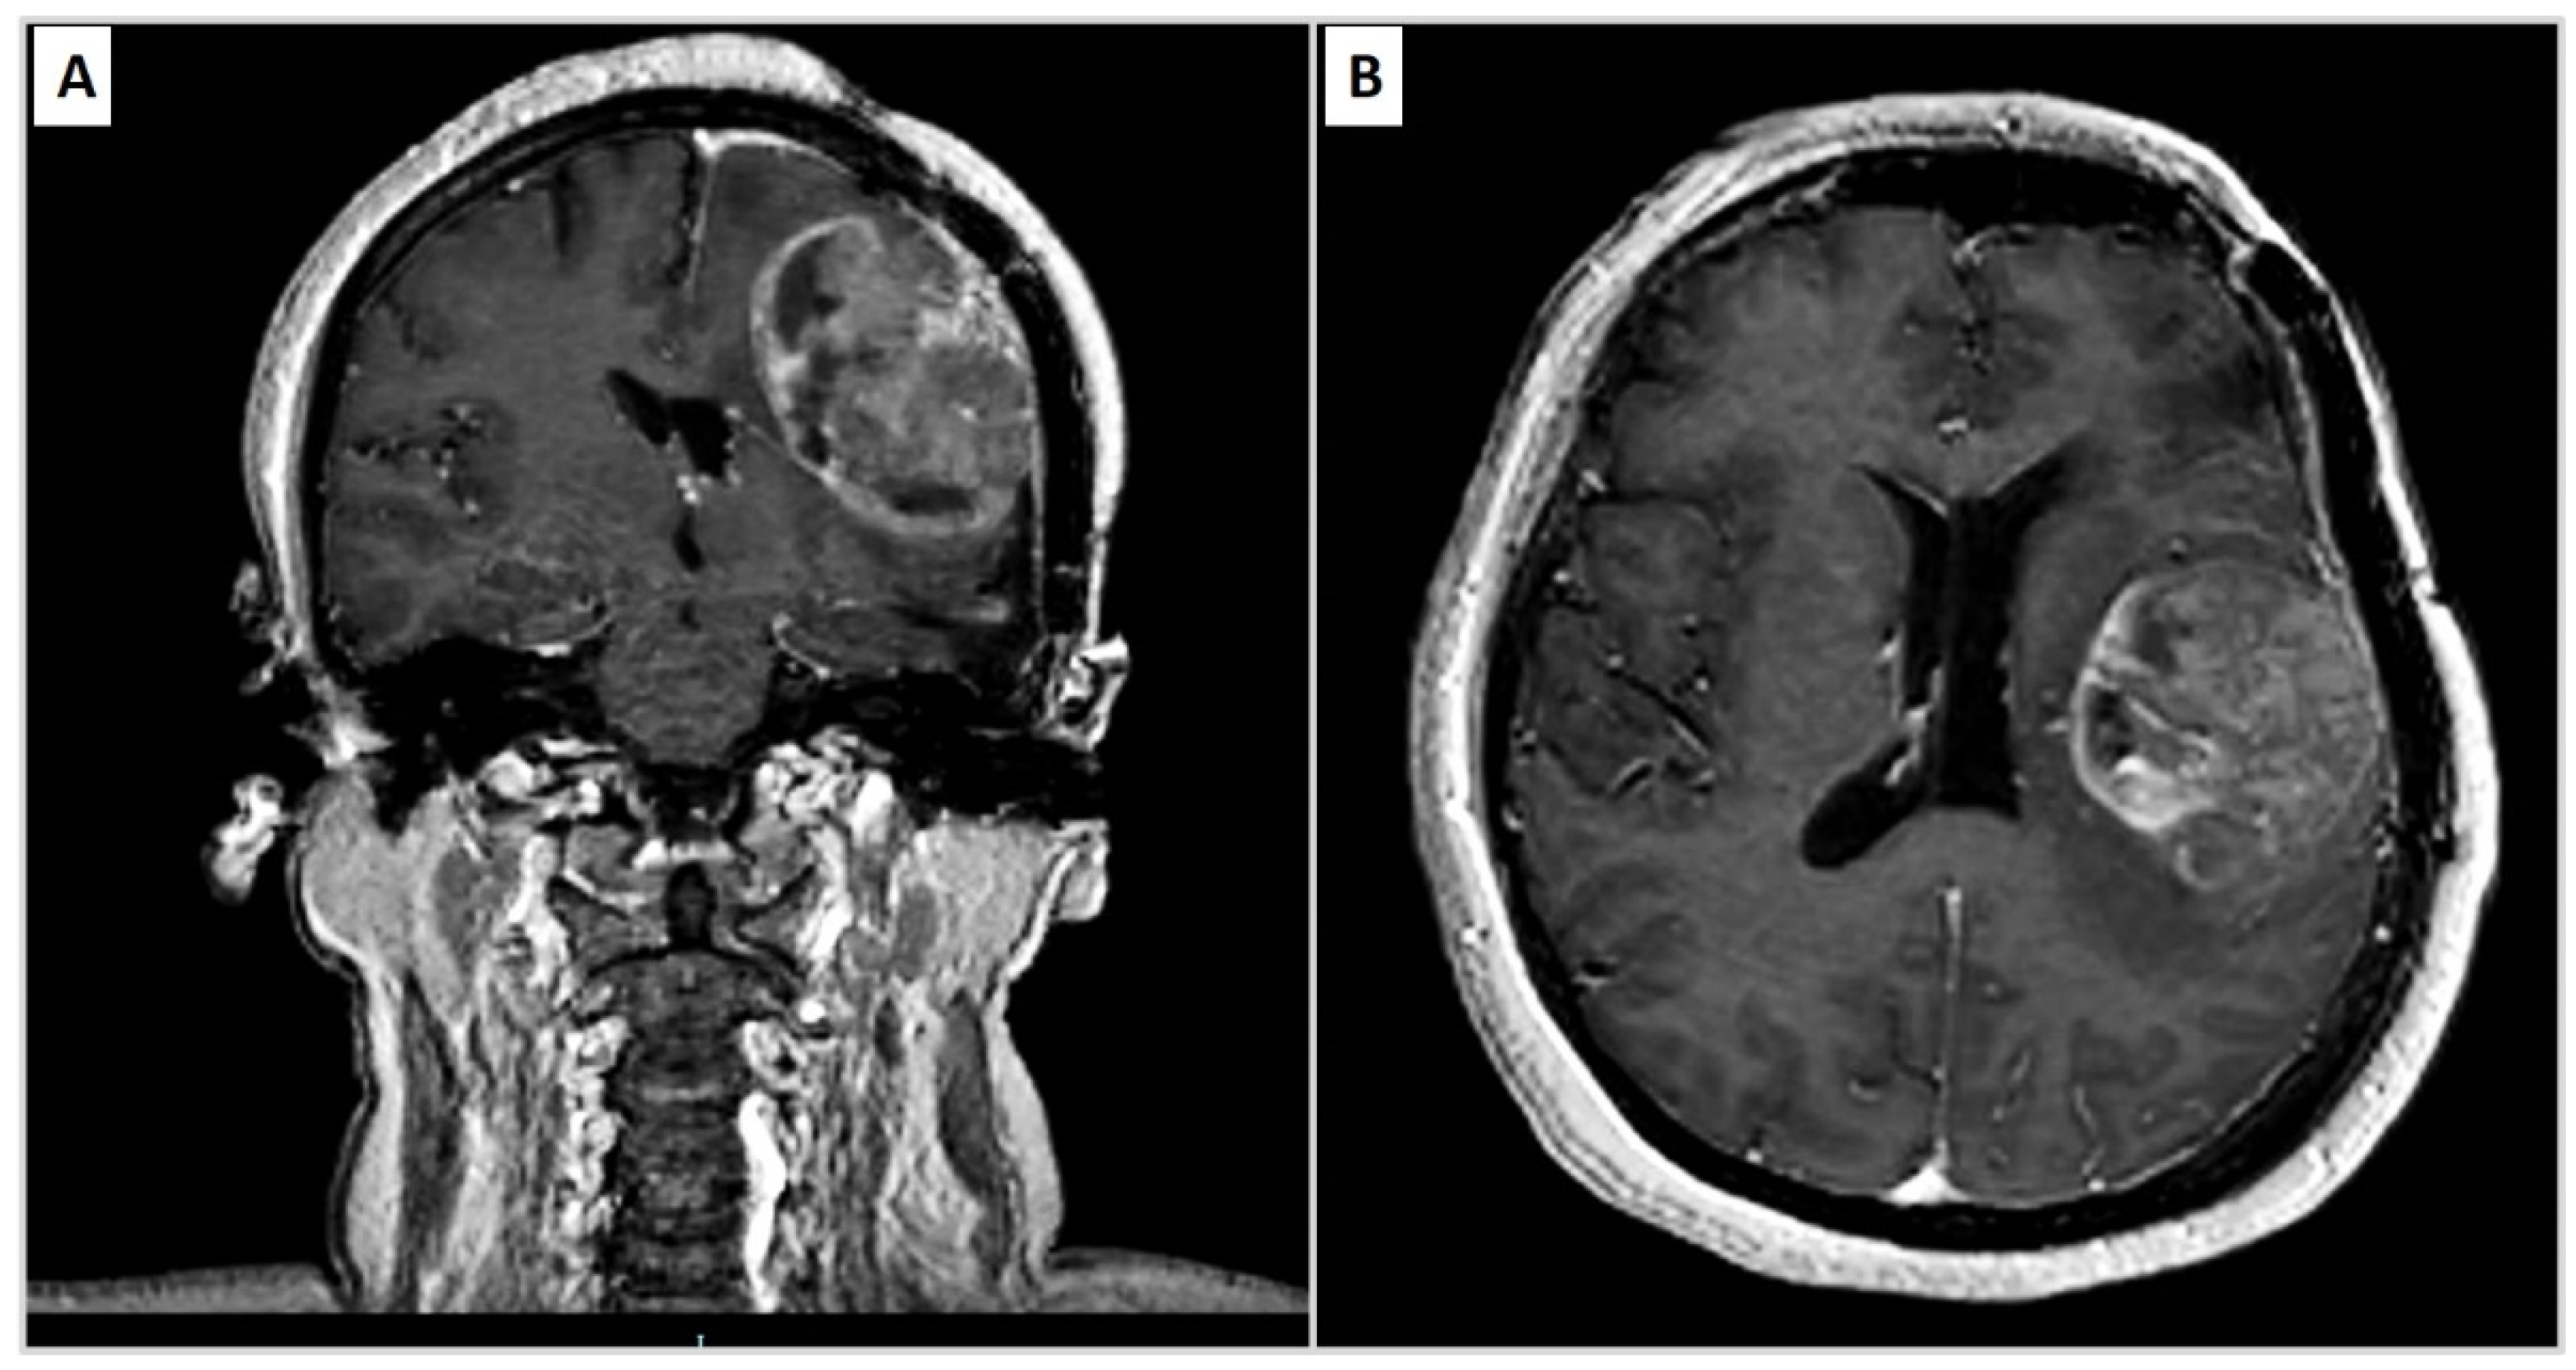

| 2015 | Headache | Recurrence of PM | Neurosurgical removal |

| 2020 | Headache, sleep disturbances and functional symptoms | Recurrence of PM | Tumour excision |